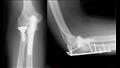

تركيب شريحة ومسامير في عملية- أرشيفية

قضت المحكمة الإدارية العليا بمجلس الدولة، بتأييد مجازاة طبيب أخصائي عظام، بخصم ستين يوماً من أجره لما نُسب إليه من عدم اتباع إجراءات العدوى، باستخدامه جهاز شنيور عادي في عملية جراحية دون انتظار جهاز الدريل الخاص بالمستشفى.

ونسبت النيابة الإدارية للطبيب، أنه خلال شهري 3 و4 2020، بدائرة عمله وبوصفه لم يؤد العمل المنوط به بدقة وخالف القواعد والأحكام المعمول بها بالقوانين واللوائح بأن لم يتبع إجراءات مكافحة العدوى وذلك باستخدامه آلات غير معقمة في عملية جراحية وهي عبارة عن مسامير ومفك طبي يوم 4/3/2020 بالمخالفة للتعليمات.

كما لم يتبع إجراءات مكافحة العدوى وذلك باستخدامه جهاز شنيور عادي في عملية جراحية دون انتظار جهاز الدريل الخاص بالمستشفى يوم 4/4/2020 بالمخالفة للتعليمات .